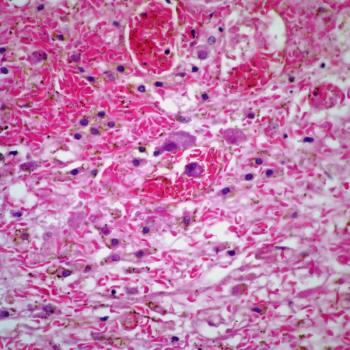

A 27-year-old woman presents with severe dyspnea. Imaging shows diffuse, bilateral infiltrates, and a biopsy is performed. What is your diagnosis?